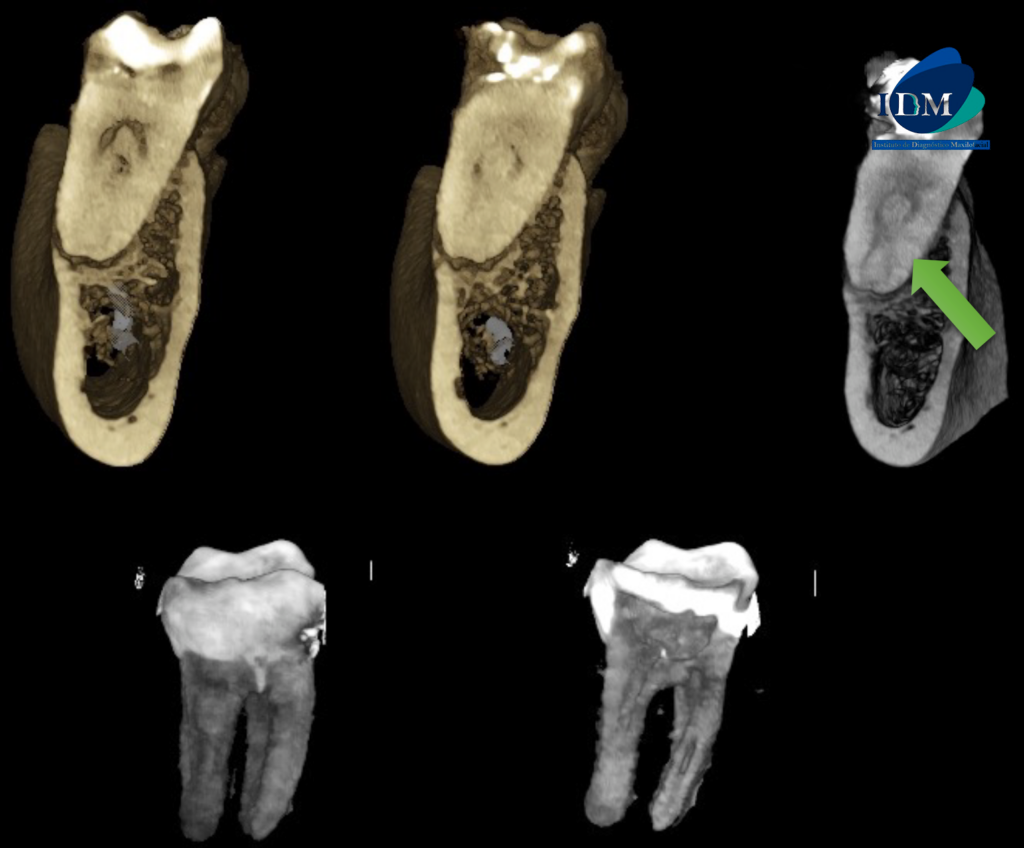

RECONSTRUCCIÓN 3D

Sin embargo respecto a la conformación de los conductos pulpares podemos observar que la raíz mesial presenta un conducto colateral hacia palatino que a su vez confluye con el conducto pulpar principal para nuevamente separarse, todo esto a nivel del tercio apical.

A La evaluación de la tomografía computarizada de campo reducido de la pieza 46 se observa material restaurador coronario amplio, una cavidad cameral amplia y ensanchamiento del espacio para el ligamento periodontal periapical en ambas raíces con el aumento de la densidad ósea compatible con osteítis circundante.